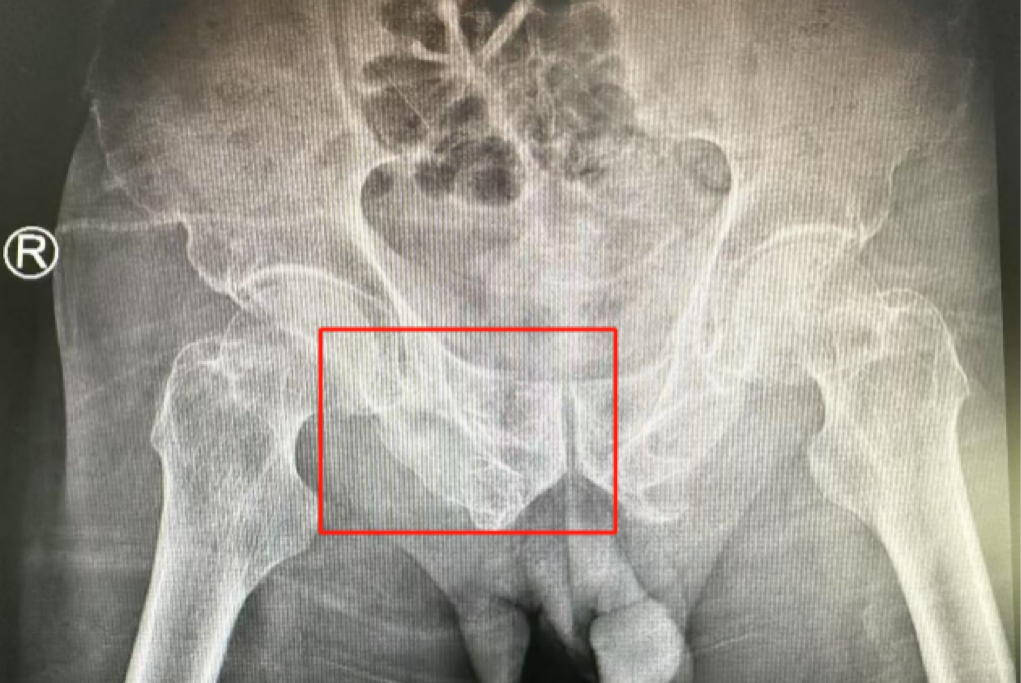

術(shù)前影像學(xué)顯示,患者的左側(cè)骶骨骨折,右側(cè)恥骨骨折、髂骨骨折,骨盆骨折分型為C型,老年脆性骨盆骨折分型為IV型,是極度不穩(wěn)定型的前環(huán)骨折和雙側(cè)后環(huán)骨折。所幸沒(méi)有明顯的骨盆出血或內(nèi)臟損傷的表現(xiàn)。

術(shù)后第二天,醫(yī)生團(tuán)隊(duì)復(fù)查X片顯示螺釘植入位置非常滿(mǎn)意,骨折基本達(dá)到穩(wěn)定復(fù)位,同時(shí),復(fù)查的全血細(xì)胞計(jì)數(shù)中,血紅蛋白指數(shù)為102g/L。術(shù)后第三天,在智能骨科病房護(hù)理團(tuán)隊(duì)及康復(fù)師的指導(dǎo)和護(hù)理下,王大爺可以坐立在床上。術(shù)后第四天,王大爺迎來(lái)了出院日,“得虧有了這么先進(jìn)的醫(yī)療技術(shù),讓我還能下地行走,謝謝你們!”

螺釘植入位置非常滿(mǎn)意